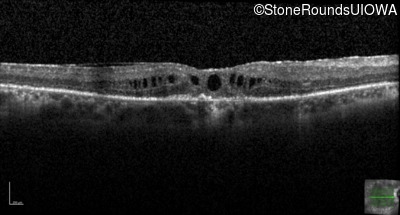

Optical Coherence Tomography - Right - 20/50 -1

Exemplar / OCT Stack

OCT Stack